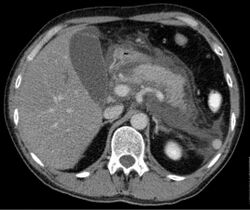

Computed tomography

Axial CT in a patient with acute exudative pancreatitis showing extensive fluid collections surrounding the pancreas

Regarding the need for computed tomography, practice guidelines state:

CT is an important common initial assessment tool for acute pancreatitis. Imaging is indicated during the initial presentation if:

- the diagnosis of acute pancreatitis is uncertain

- there is abdominal distension and tenderness, fever >102 F (38,9 C), or leukocytosis

- there is a Ranson score > 3 or APACHE score > 8

- there is no improvement after 72 hours of conservative medical therapy

- there has been an acute change in status: fever, pain, or shock

CT is recommended as a delayed assessment tool in the following situations:

- acute change in status

- to determine therapeutic response after surgery or interventional radiologic procedure

- before discharge in patients with severe acute pancreatitis

Abdominal CT should not be performed before the first 12 hours of onset of symptoms as early CT (<12 hours) may result in equivocal or normal findings.

CT findings can be classified into the following categories for easy recall:

- Intrapancreatic – diffuse or segmental enlargement, edema, gas bubbles, pancreatic pseudocysts and phlegmons/abscesses (which present 4 to 6 wks after initial onset)

- Peripancreatic / extrapancreatic – irregular pancreatic outline, obliterated peripancreatic fat, retroperitoneal edema, fluid in the lessar sac, fluid in the left anterior pararenal space

- Locoregional – Gerota's fascia sign (thickening of inflamed Gerota's fascia, which becomes visible), pancreatic ascites, pleural effusion (seen on basal cuts of the pleural cavity), adynamic ileus, etc.

The principal value of CT imaging to the treating clinician is the capacity to identify devitalised areas of the pancreas which have become necrotic due to ischaemia. Pancreatic necrosis can be reliably identified by intravenous contrast-enhanced CT imaging,[20] and is of value if infection occurs and surgical or percutaneous debridement is indicated.